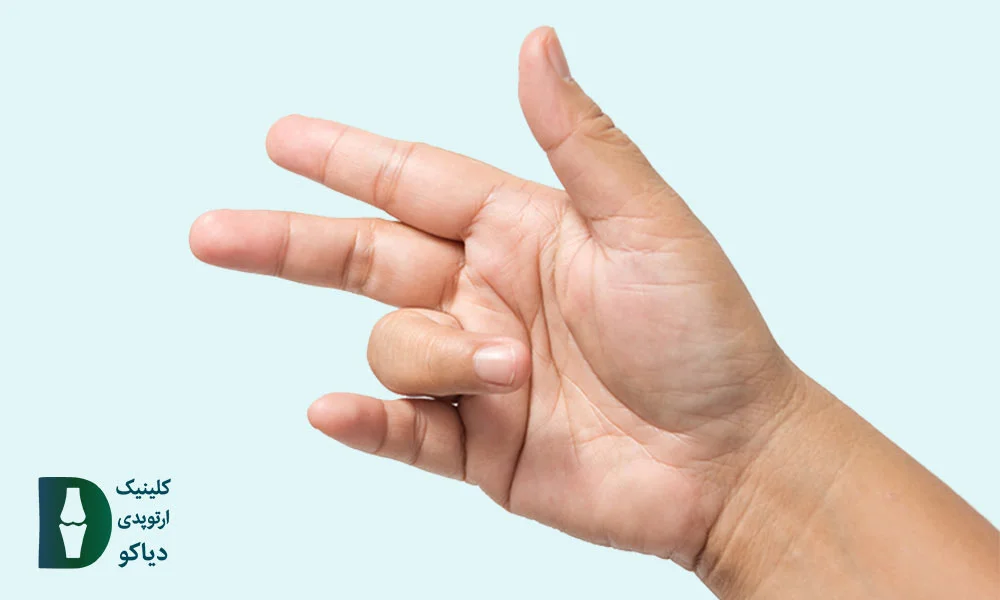

اگر هنگام باز و بستهکردن انگشتان، احساس قفلشدگی، صدای تق یا درد دارید، ممکن است دچار عارضهی انگشت ماشهای شده باشید. این وضعیت معمولاً در یک انگشت بروز میکند، اما اگر چند انگشت همزمان درگیر شوند، میتواند نشانهای از بیماریهای زمینهای مانند دیابت یا آرتریت روماتوئید باشد.

در اغلب موارد، انگشت شست، میانی یا حلقه بیشتر از سایر انگشتها دچار این مشکل میشوند. با این حال، برای تشخیص دقیق، انجام یک تست ساده در خانه میتواند مفید باشد.

![]() صدا یا حس «تقزدن» هنگام صاف شدن انگشت: نشانهای از گیر کردن تاندون در غلاف خود (علامت رایج در گرید 2 و 3).

صدا یا حس «تقزدن» هنگام صاف شدن انگشت: نشانهای از گیر کردن تاندون در غلاف خود (علامت رایج در گرید 2 و 3).

![]() نیاز به کمک دست دیگر برای صاف کردن انگشت: نشانهی پیشرفت بیماری و محدودیت عملکرد عضلات (گرید 3a).

نیاز به کمک دست دیگر برای صاف کردن انگشت: نشانهی پیشرفت بیماری و محدودیت عملکرد عضلات (گرید 3a).